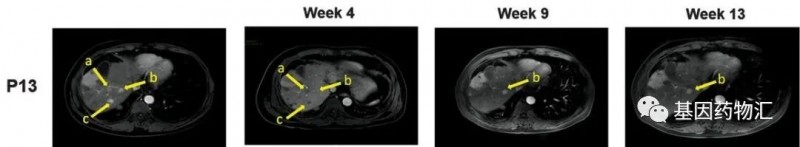

另一位患者为52岁的男性,多灶性肝细胞癌的病史更是长达3.7年。该患者曾经接受过5次经导管动脉化疗栓塞手术和11次热消融治疗。检测时,患者的GPC3 IHC染色评分同样为3+。

MRI扫描共锁定了患者的3个病灶(黄色箭头标注的a、b、c病灶),从治疗4周后,a和c病灶完全消失,b病灶从14.2 × 13.4 mm略微缩小至13.9 × 13.0 mm。

治疗的过程中,患者经历了2级的细胞因子释放综合症,但已经通过对应的治疗从中康复。截至病例发布时,患者仍然保持生存,CAR-GPC3 T细胞疗法已经为这位患者带来了99天的持续缓解,以及超过385天的生存期,这个数据还在增涨!